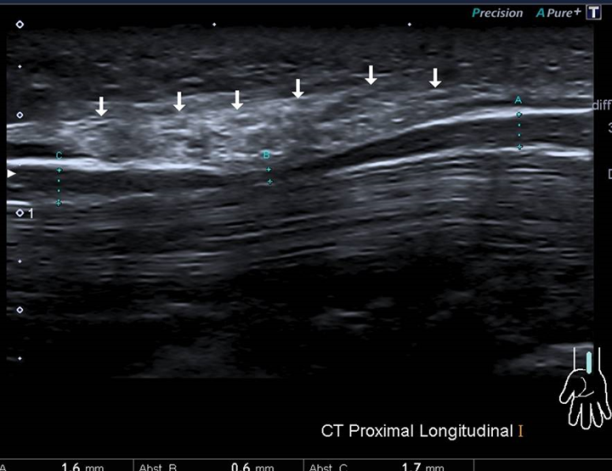

„Mit hochauflösenden Ultraschallgeräten können wir den Nerv und die umliegenden Strukturen mit großer Detailschärfe abbilden und erkennen, ob dieser beispielsweise durch eine Schwellung der Sehnenscheiden oder durch knöcherne Strukturen bedrängt wird oder sogar ein Nerventumor vorliegt“, erklärt der Berliner DEGUM-Experte Dr. med. Josef Böhm. Außerdem ermögliche es der Ultraschall, die Einengung zu lokalisieren: Oftmals liege das Problem gar nicht auf Höhe des Karpaltunnels, sondern weiter oben am Unter-oder Oberarm. Dr. Böhm: „Für eine genaue Diagnostik brauchen wir sowohl die Elektrophysiologie, die uns Informationen über die Reizweiterleitung liefert, als auch die Neurosonografie“.

Ergänzend zur elektrophysiologischen Untersuchung, liefere die Neurosonografie Informationen über Ursache der Kompression und Lage der Engstelle. Diese seien für eine zielgerichtete Behandlung und bei der Entscheidung für oder gegen eine Operation sehr wichtig, so die Fachgesellschaft.